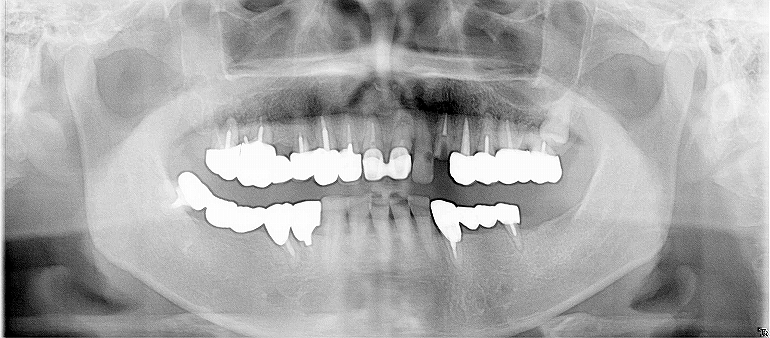

Vol.3

Before

奥歯で咬むと痛い、冠せが次々とれてくるのでどうにかしたいが、

入れ歯は避けたい。

After

右上2本、左下1本、下前歯4本、

計7本インプラント埋入。